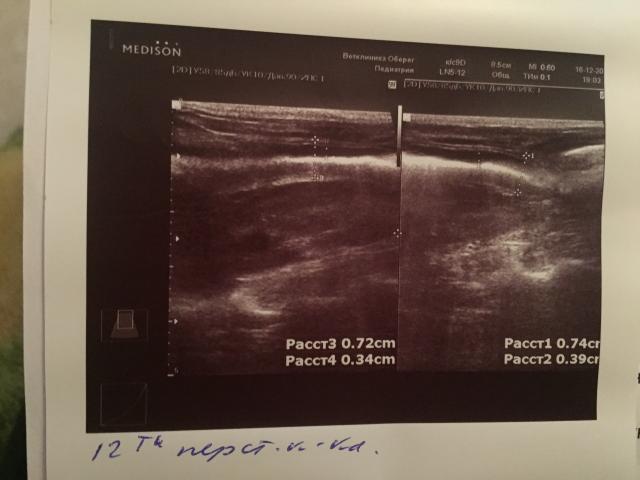

Если можно, то немного подробнее. На основании чего вам поставили такой диагноз, только на основании проведенного УЗИ? Может быть, собаке брали какие-то анализы? Если да, то выложите, пожалуйста, здесь их результаты. Если только данные УЗИ, то это разговор ни о чем (я имею ввиду панкреатит). Гастрит по данным УЗИ вообще не ставят.

К сожалению, ничего не могу рассмотреть. Попробуйте сами прочесть описание с фото. Если сможете, сделайте снимок более качественным. Или можно снять крупнее по частям. Может быть, тогда буквы будут видны более четко.

Спасибо, фотографии четкие. Я все прочитал. Как я и думал, там и "не пахнет" никаким гастродуоденитом, а тем более, панкреатитом.